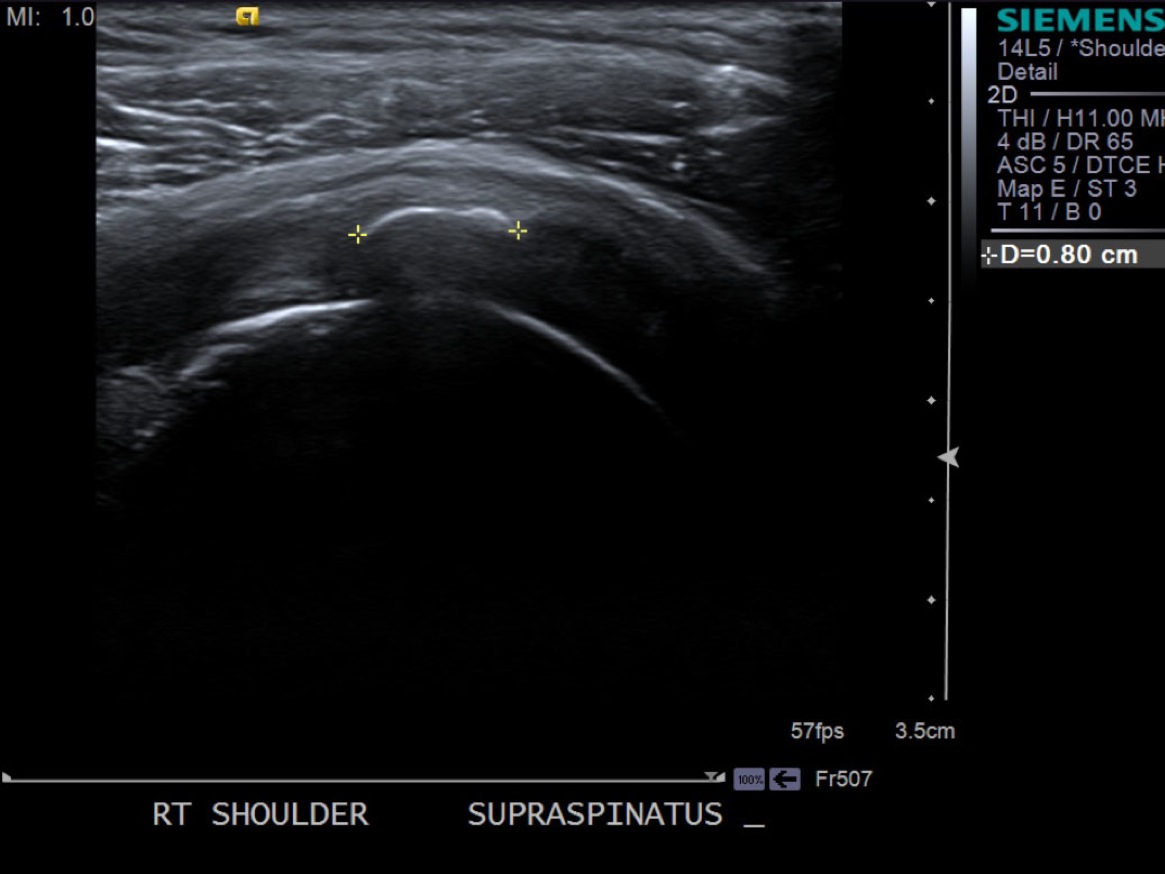

3.Scan patient looking for calcific tendinosis deposition typically in the supraspinatus tendon. Measure size of largest deposits.

Long axis view of supraspinatus tendon with calcific deposit

Short axis view of supraspinatus tendon with calcific deposit